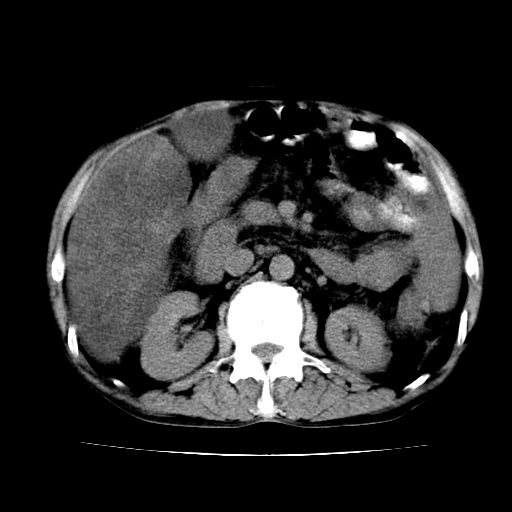

男,55岁,发现“肝硬化”5年,现腰疼、腹胀10余日,巩膜黄染、腹稍胀,肝肋下3指,质硬无压疼,移动性+,血生化:总胆、直胆、间胆均升高。

g1:肝硬化、脾大、腹水。

2:脂肪肝。

3:弥漫性肝癌待排。

肝硬化,脾大,腹水

脂肪肝

肝内多发低密度灶(建议增强扫描除外肝癌)

肝脾肿大,脂肪肝,腹水。建议增强除外肝癌。